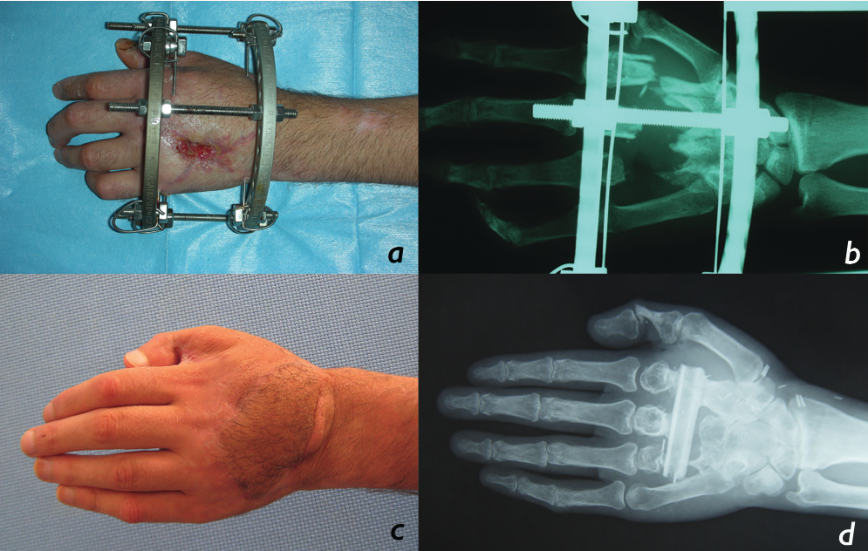

Six patients with gunshot injuries of the hand, resulting in composite metacarpal loss, were treated with free vascularized fibular flap. All patients were male with a mean age of 23 years. The patients underwent a careful clinical and radiologic evaluation, and all injuries were clarified before surgery. The deep and superficial palmar arc of the injured hand was assessed with Doppler ultrasound. The bony defects consisted of 1 metacarpal bone in 4 patients, 2 metacarpal bones in 1 patient, and 3 metacarpal bones in 1 patient. The patient who lost 2 metacarpal bones received a double-barrel osteocutaneous fibular flap. In 2 patients, the fibular bone segment was split longitudinally for size adjustment to the native metacarpal bones. In the last patient, the defect involved the second, third, and fourth metacarpal shafts, and the fibular flap was used transversely to reconstruct the bony defect (Figures 1, 2, and 3). Soft tissue defects were observed at the dorsum of the hand in 5 patients and at the thenar region in 1 patient. All patients had various degrees of extensor and/or flexor tendon injuries. The characteristics of the patients’ injuries are seen in Table 1.

All patients were referred to our department from other hospitals after an initial intervention that included stabilization, initial debridement, and bone fracture stabilization with K wires or external fixators. Following admission to our department, additional debridement and definitive reconstruction were performed within 2 days. The fibular bone was osteotomized to replace the single or adjacent missing bone segments. During the treatment of the second and third patients, the fibular bone could hardly be inserted to the defects because of the size mismatch. Therefore, in the fourth and fifth patients, the fibular bone was split longitudinally to reduce the size, which enabled better adjustment to the defect (Figure 4). To split the fibula following the harvest of the flap, the fibular cortex (which does not carry the fibular pedicle or septocutaneous perforators) was excised via longitudinal osteotomy. By this way, we obtained a narrower fibular bone segment. The fibula segment was fixed to the bone remnants with K wires. The flexor tendons were repaired primarily. The extensor tendons were repaired either primarily or with tendon grafts. K wires were removed at 6 weeks postoperatively.

All flaps survived with no major postoperative complications requiring surgical intervention. Venous congestion was observed in the skin islands of the second and third cases, which were treated by using medical leeches. We thought that size discrepancy might contribute to the venous congestion in the skin island by causing compression of the perforators. Therefore, in the following 2 patients (fourth and fifth cases), the fibular bone segment was split longitudinally for size match and better adjustment during inset of the flap (Table 1). We have not observed any vascular problems in patients with split fibular flap reconstruction. The mean follow-up period of the 6 patients was 18 months (range, 12-26 months). Clinical and radiological union was established in all cases after an average of 2 months. No delayed bone resorption or migration was observed.